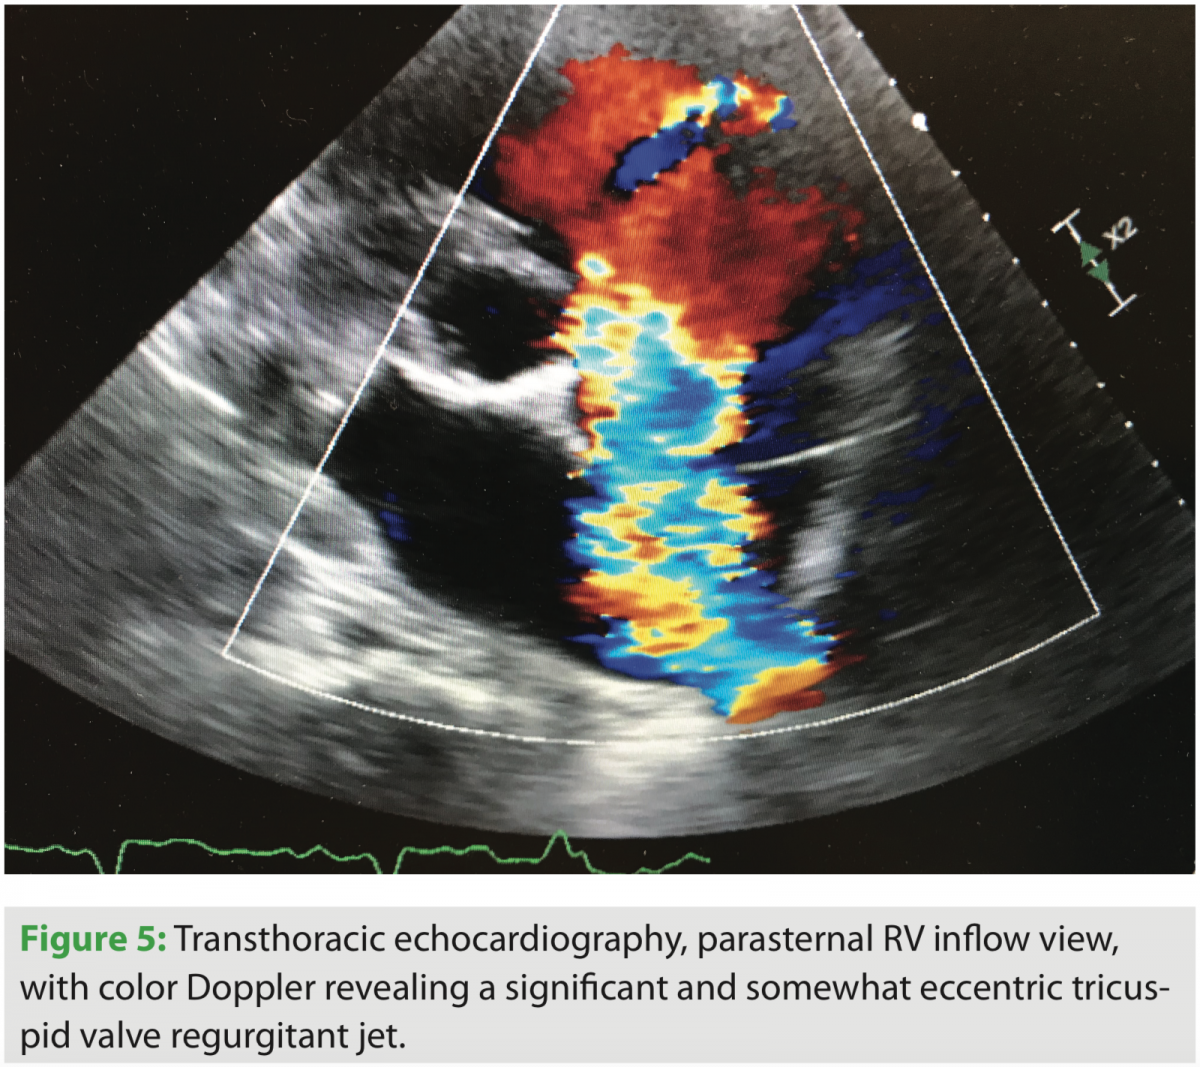

After admission and diuresis, significant symptomatic improvement occurred, and the patient was nearing his perceived dry weight based on initial clinic visits and recorded weights from home. Standard two- and three-dimensional transthoracic echocardiography were performed, and significant tricuspid valve regurgitation was seen. The course of the right ventricular lead can be seen in several views, along with its interaction with the TV leaflet and interventricular septum (Figures 1, 2, and 4). Corresponding tricuspid valve dysfunction is appreciated with severe tricuspid valve regurgitation on Doppler echo images (Figures 3 and 5). The RV was felt to be moderately dilated with a mid-RV diameter of 3.5 cm. Significant RV systolic dysfunction was seen and felt to be moderate with a tricuspid annular plane systolic excursion (TAPSE) of 1.25 cm. The tricuspid valve regurgitation was severe with a vena contracta width of 0.9 cm and PISA radius of 1.0 cm. LV systolic function was essentially unchanged, with an EF of 25%. The bioprosthetic aortic valve was well seen and without significant dysfunction.